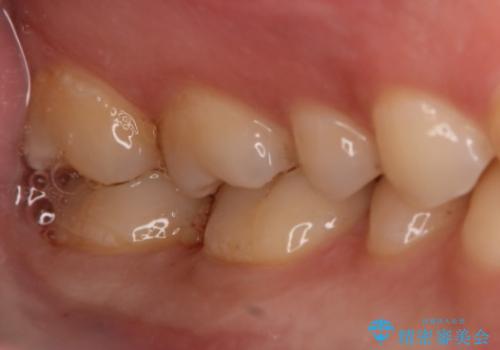

- 右下6・7番の治療のやり変えを主訴に来院された患者様です。

保険の材料が劣化し中で虫歯が進行しているため、古い材料と虫歯を全て除去した上で詰め直す必要がありました。

切削量・形態を考慮し、セラミックインレーでの治療を計画しました。

虫歯が深い場合、痛みなどの症状が出る可能性がありますが、経過は良好でご本人も満足されています。